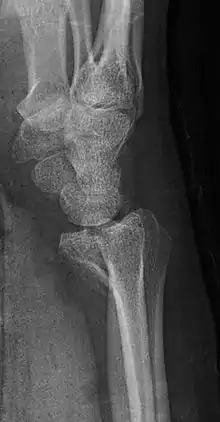

| A palmar Barton's fracture of the right wrist, as shown on a 3D-rendered CT scan | |

A Barton's fracture is a type of wrist injury where there is a broken bone associated with a dislocated bone in the wrist, typically occurring after falling on top of a bent wrist.[1] It is an intra-articular fracture of the distal radius with dislocation of the radiocarpal joint.[2]

There exist two types of Barton's fracture – dorsal[3] and palmar, the latter being more common. The Barton's fracture is caused by a fall on an extended and pronated wrist increasing carpal compression force on the dorsal rim. Intra-articular component distinguishes this fracture from a Smith's or a Colles' fracture. Treatment of this fracture is usually done by open reduction and internal fixation with a plate and screws, but occasionally the fracture can be treated conservatively.[4]